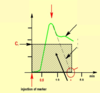

Give the contractile components of the myocardium

- Heart muscle fibres (working fibres)

- Stretching enhances their force-generating capability

Give the non-contractile components of the myocardium

- Serially attached elastic elements (SEC)

- Parallelly attached elastic elements (PEC)